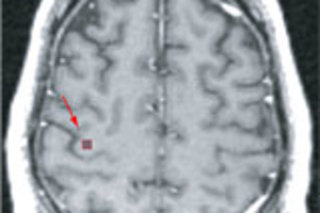

The BrainGate implant's array of 100 hair-thin electrodes delves the cortex and eavesdrops on neurons that normally control hand and arm movement.

Neuroscientist John Donoghue of Brown University has brought us a big step closer to the day when people can interact with computers directly through the power of thought. In July he and his team published a paper in Nature outlining remarkable progress in picking up brain signals with implanted electrodes and using those signals to control a range of devices.

The experiments were conducted on a 25-year-old Massachusetts man paralyzed from the neck down. In 2004, surgeons placed a tiny 100-electrode array in his primary motor cortex, the brain region that controls voluntary movement, to collect electrical impulses from nerve cells and send them to a series of signal processors. Donoghue and his colleagues then supervised as the computer translated the man's thoughts of moving his arm and hand into the actual movement of external devices. On the first day the system was up and running, he was able to master the technique. He could move a computer cursor, play a video game, open e-mails, draw a crude circle, operate a television remote control, and even move a prosthetic hand and arm — using nothing other than his will.

The same basic brain-computer interface system had been tested earlier in monkeys, and a group in Georgia implanted electrodes in people as far back as the 1990s. But no other group has used implanted electrodes to monitor so many human neurons at once or had such impressive results.

The system was removed from the original subject after 14 months. It is now being tested on three other patients, including one with ALS. Neurologist Leigh Hochberg, the lead author on the paper with Donoghue, hopes that the current trials are the first step toward giving severely disabled people an unprecedented degree of independence. "The participants in these trials are pioneers," he says.